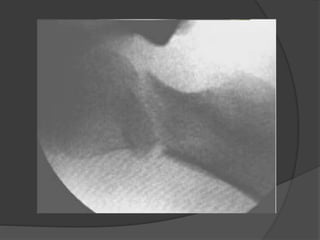

Clasificación Delbet - ColonnaTipo I: transepifisiaria A: No luxada B: luxada  Tipo II: transcervical  Tipo III: basecervical  TipoIV: Intertrocanterica

Tipo 1  Menosfrecuente  Incidencia del 8% de las fracturas del cuello  Presentan necrosis avascular en el 70% de los casos  Mejor pronostico en menores de 2-3 años

Tipo 2  Representanel 46% de los casos  77% desplazadas  Se presenta necrosis avascular en el 45-50% de los casos  Necrosis avascular directamente proporcional al desplazamiento

Tipo 3  Ocupael segundo lugar de frecuencia  Incidencia del 34%  Presentan necrosis avascular en el 30% de los casos  Riesgo de necrosis avascular directamente proporcional al desplazamiento  Cierre prematuro de la fisis en 25%